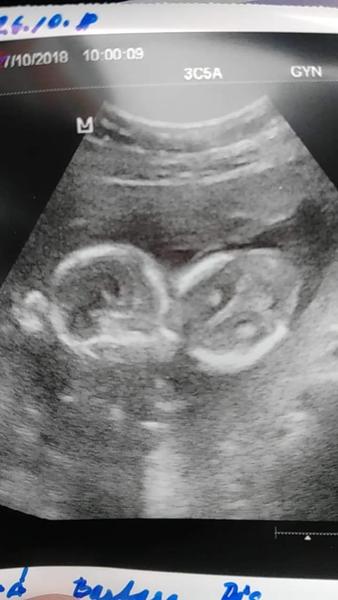

tak my máme dnešní kontrolu taky úspěšně za sebou. lásky se tam k sobě krásně tulili. a prý to druhý vážně vypadá na naší vysněnou Anežku. To jsem hrozně ráda, apsoň nebudu muset hledat nikoho, kdo by pak v porodnici vyměnil holčičku za kluka :D :D ještě mi dělala nějaká vyšetření kvůli případnému předčasnému porodu. 8.11. na druhý screening a pak cukrovka :D